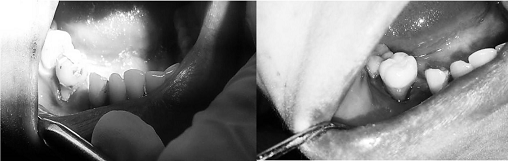

В ході власної практичної апробації даного методу

реставрації реконструкція форми поєднувалась з корекцією кольорових

характеристик зубів та ясен, а об’єм втручання визначався в залежності від

розмірів дефекту або дефіциту твердих і м’яких тканин (рис. 1-2).

Рис. 2. 46 зуб: вигляд до та після відновлення

дефекту рожевим композитом

В результаті проведених реставрацій вдалось

відновити форму та розмір проблемних зубів, параметри їх світлопроникності,

особливо опалесценції, транслюценції та прозорості на межі рожевої та білої

естетики, а також особливості структура поверхні в області ясен. Аналогічно

успішні результати відновлення пришийкових дефектів в області рецесії ясен були

описані в роботах Wahbi M. A., Tayeb H. (2013) [11] та Dhingar D., Gupta A. K.

(2016) [12].